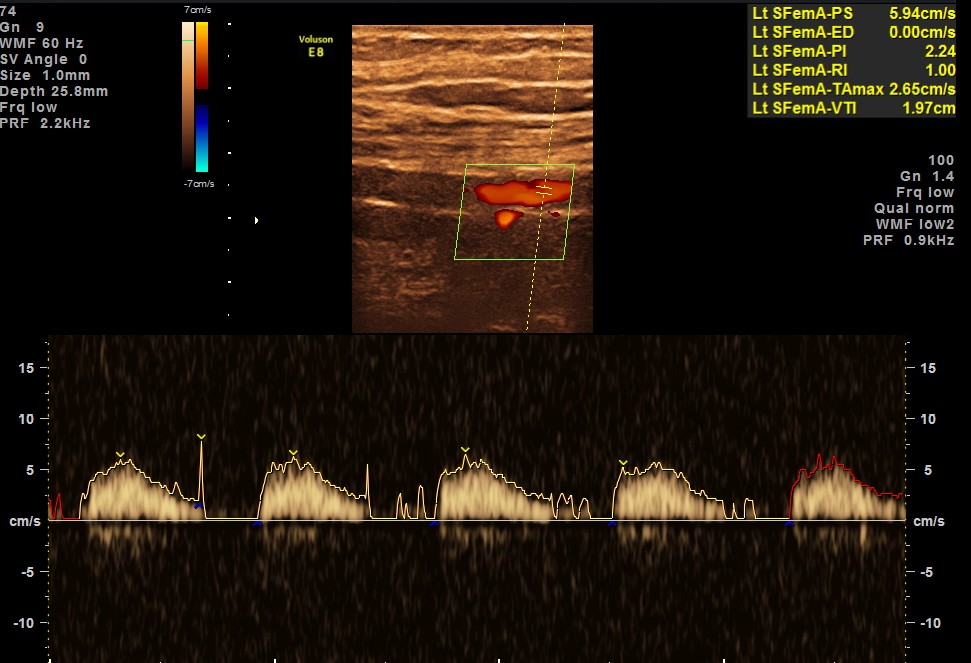

BOTH DORSALIS PEDIS ARTERIES SHOW LOSS OF ARTERIAL TONE AND MONOPHASIC FLOW.

EXTENSIVE ATHEROSCLEROTIC OBSTRUCTIVE DISEASE OF THE LOWER LIMB ARTERIES WAS SEEN WITH THE CHANGES IN THE RIGHT COMMON FEMORAL ARTERY BEING MORE THAN THE LEFT CFA.